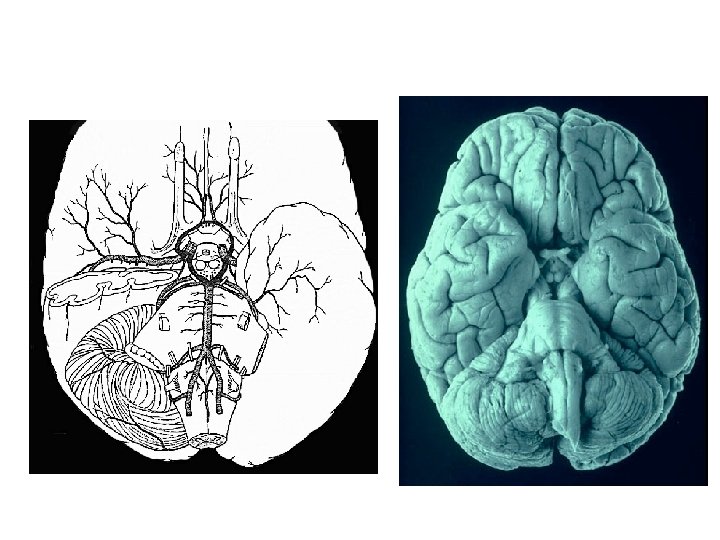

ACA MCA PCA BA VA ICA